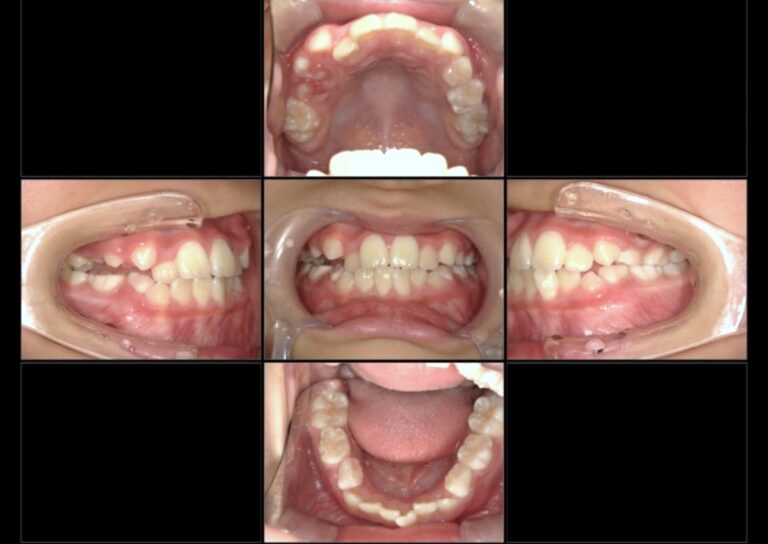

小児矯正症例:八重歯、上下の歯のジグザグ(叢生)

| 主訴 | 八重歯、上下の歯のジグザグ(叢生) |

| 治療内容 | 日中1時間以上の装置装着、アクティビティ(約10分の筋機能訓練)、数ヶ月間の固定式装置の装着 |

| 治療期間 | 約1年(現在も永久歯への生え変わりを診るために経過観察中) |

| 費用 | 契約時:330,000円 管理料:2,750円/月1回 |

| 治療のリスク | 指示通りの通院、装置装着、アクティビティが行われていないと治療結果が損なわれることがある。 |